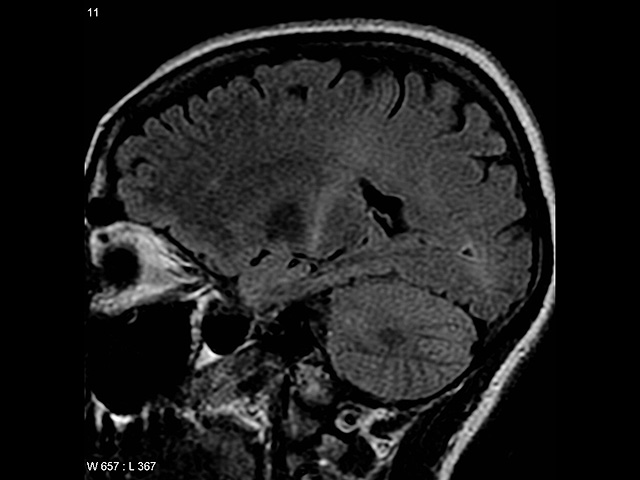

Боковой амиотрофический склероз (БАС) – неизлечимое нейродегенеративное заболевание, от которого страдают миллионы людей по всему миру. Этим заболеванием страдал знаменитый физик Стивен Хокинг. Он прожил с этой болезнью 50 лет и стал удивительным исключением: обычно пациенты, страдающие БАС, живут 3-5 лет.

Ученые выяснили, что мышечные клетки производят малые молекулы РНК – микроРНК-126 – и отправляют их через синапс в нервную клетку. Эти молекулы предотвращают избыточную выработку белка TDP-43 в нервно-мышечном соединении. При БАС мышцы производят меньше микроРНК-126, чем необходимо. Это приводит к накоплению белка TDP-43. Избыток белка формирует токсичные скопления, которые атакуют митохондрии – энергетические станции нейронов.